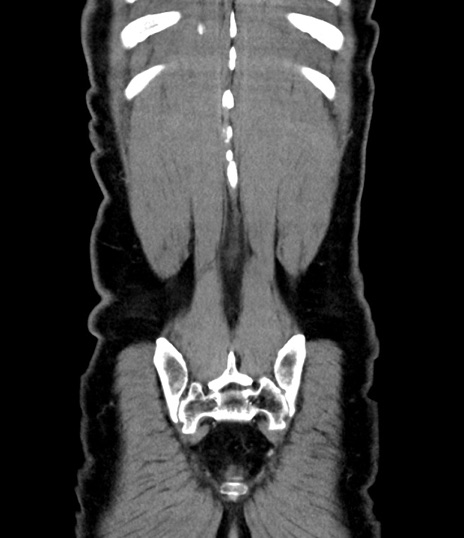

横断像

【症例】 60歳代男性

【主訴】 黒色吐物

【現病歴】 4日前から嘔気自覚、2日前の朝食後にも嘔気あり、自分で手で嘔吐反射起こし嘔吐したところ血が混ざっていたため受診。

【既往歴】 5年前汎発性腹膜炎を伴う急性虫垂炎で手術、高血圧、前立腺肥大症、高脂血症

【身体所見】 腹部正中に手術癩痕あり 腹部平坦・軟圧痛なし膨満感あり

【データ】WBC 8400、CRP 4.54